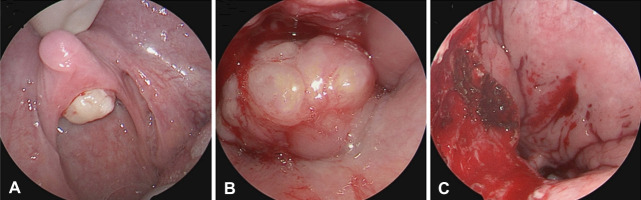

Adenomatous polyposis coli (APC) is a tumor suppressor gene expressed throughout the body. APC mutations increase the risk of malignancy and are often characterized by syndromes that encompass a spectrum of neoplastic manifestations, such as familial adenomatous polyposis (FAP). We present a rare case of palatal peripheral nerve sheath tumor in the context of APC gene mutation. A 17-year-old male with a significant history of FAP presented to our clinic with globus sensation for 5 months with increasing discomfort. Flexible nasolaryngoscopy revealed a pedunculated lesion attached to the posterior surface of the soft palate. Imaging was obtained and confirmed a soft tissue homogenous mass contiguous with the soft palate. Endoscopic-assisted transoral resection was performed and pathologic features were consistent with schwannoma. We also discuss the spectrum of benign neoplastic lesions. Current literature fails to describe pharyngeal masses in the setting of APC gene mutations. The purpose of this case report is to describe a patient presentation of a symptomatic pharyngeal tumor with a known APC gene mutation and explore the differential diagnoses that must be considered.